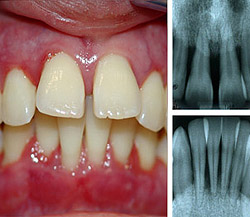

Клиническая картина пародонтоза: оголение шеек зубов (часть зуба около десны) и корней, рецессия (опущение) десен, [4] зуб становится «вытянутым», при этом воспаление, отечность и кровоточивость отсутствует, цвет десны бледно-розовый (может быть бледнее цвета здоровой десны), десна плотно охватывает зуб (в отличие от воспалительного заболевания тканей пародонта – гингивита и пародонтита).

При пародонтозе изменения затрагивают невидимую для глаз человека часть — костную ткань челюсти. Изменения, которые происходят в ней, приводят к подвижности зубов и как результат — их удалению. На уровне кости изменения затрагивают процесс образования костной ткани: новая ткань на фоне разрушения не успевает восстановиться с помощью специальных клеток, строящих ее. Ткань кости челюсти постепенно убывает. Этот процесс виден только на рентгенограмме челюстей. [5]

Для легкой степени тяжести характерно отсутствие жалоб, изменения в костной ткани видны только на рентгеновском снимке.

Средняя степень пародонтоза характеризуется оголением шеек зубов и корней (до 3мм), на рентгеновском снимке можно заметить снижение высоты костных перегородок между зубами, достигающее половины высоты корней зубов. Пациенты могут жаловаться на появление неприятных ощущений в деснах, зуда, на изменение положения зубов (наклон, смещение в виде веера).

При тяжелой степени пародонтоза оголение шеек зубов и корней доходит до 5 мм, костные перегородки разрушены уже на 2/3 длины корней зубов, что приводит к появлению подвижности зубов и изменению их положения в челюсти и смыкания между собой.

Степень разрушения кости челюстей исследуют с помощью рентгенологического исследования (панорамная рентгенография, компьютерная томография), по которой можно различить стадии пародонтоза. Плотность костной ткани изучают с помощью эхоостеометрии. Изучение состава слюны и микрофлоры полости рта дает большие возможности в терапии пародонтоза. [8]